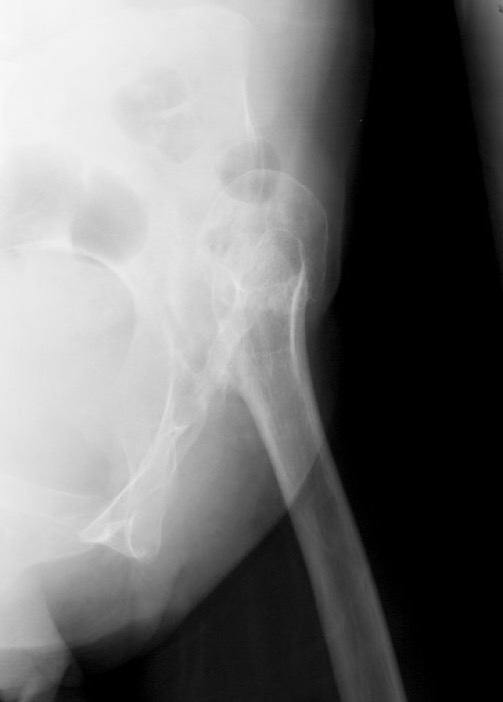

Crowe I

Crowe II

Crowe III

Crowe IV